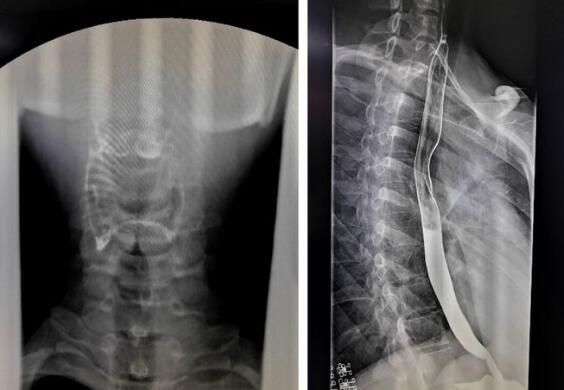

數(shù)字化胃腸機拍攝的上消化道造影圖

隨著數(shù)字化胃腸機臨床應(yīng)用越來越廣泛,其功能性也大大增強,那么數(shù)字化胃腸機到底能做哪些檢查呢?其功能你有了解多少?1、上消化道造影,能顯示咽部到十二指腸的影像。